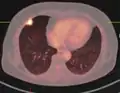

Lobulated nodule.[9]